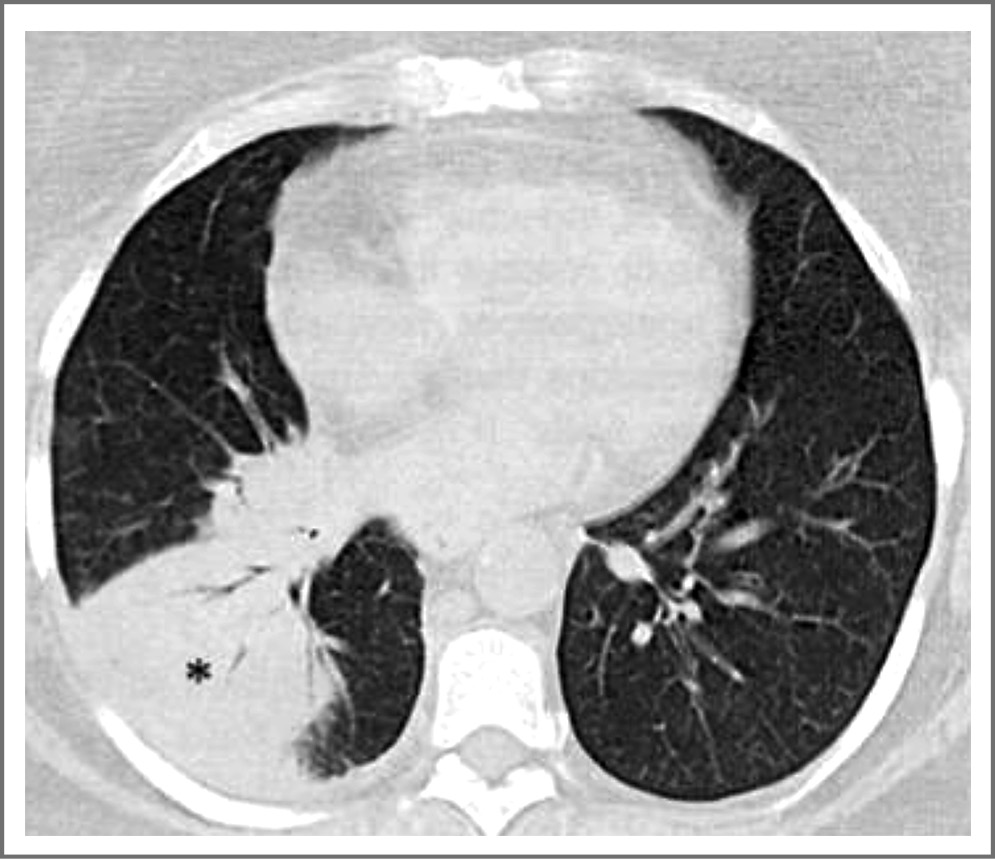

На рис. 1 демонстрируется компьютерная томограмма (КТ) мужчины 42 лет, у которого в последние 2 сут отмечены высокая температура, выраженное общее недомогание, присоединился сухой непродуктивный кашель и дыхательный дискомфорт, положительный тест на SARS-CoV-2. Феномен «матового стекла» на КТ носит диффузный характер.

Рис. 1. КТ органов грудной клетки у мужчины 42 лет, феномен «матового стекла» носит диффузный характер. / Fig. 1. The chest computed tomography (CT) of a 42-year-old man, the phenomenon of "matte glass" is diffuse.